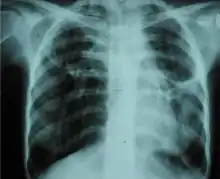

Chest X-ray showing bilateral fibrosis and pleural thickening in infection with non-tuberculosis mycobacteria.